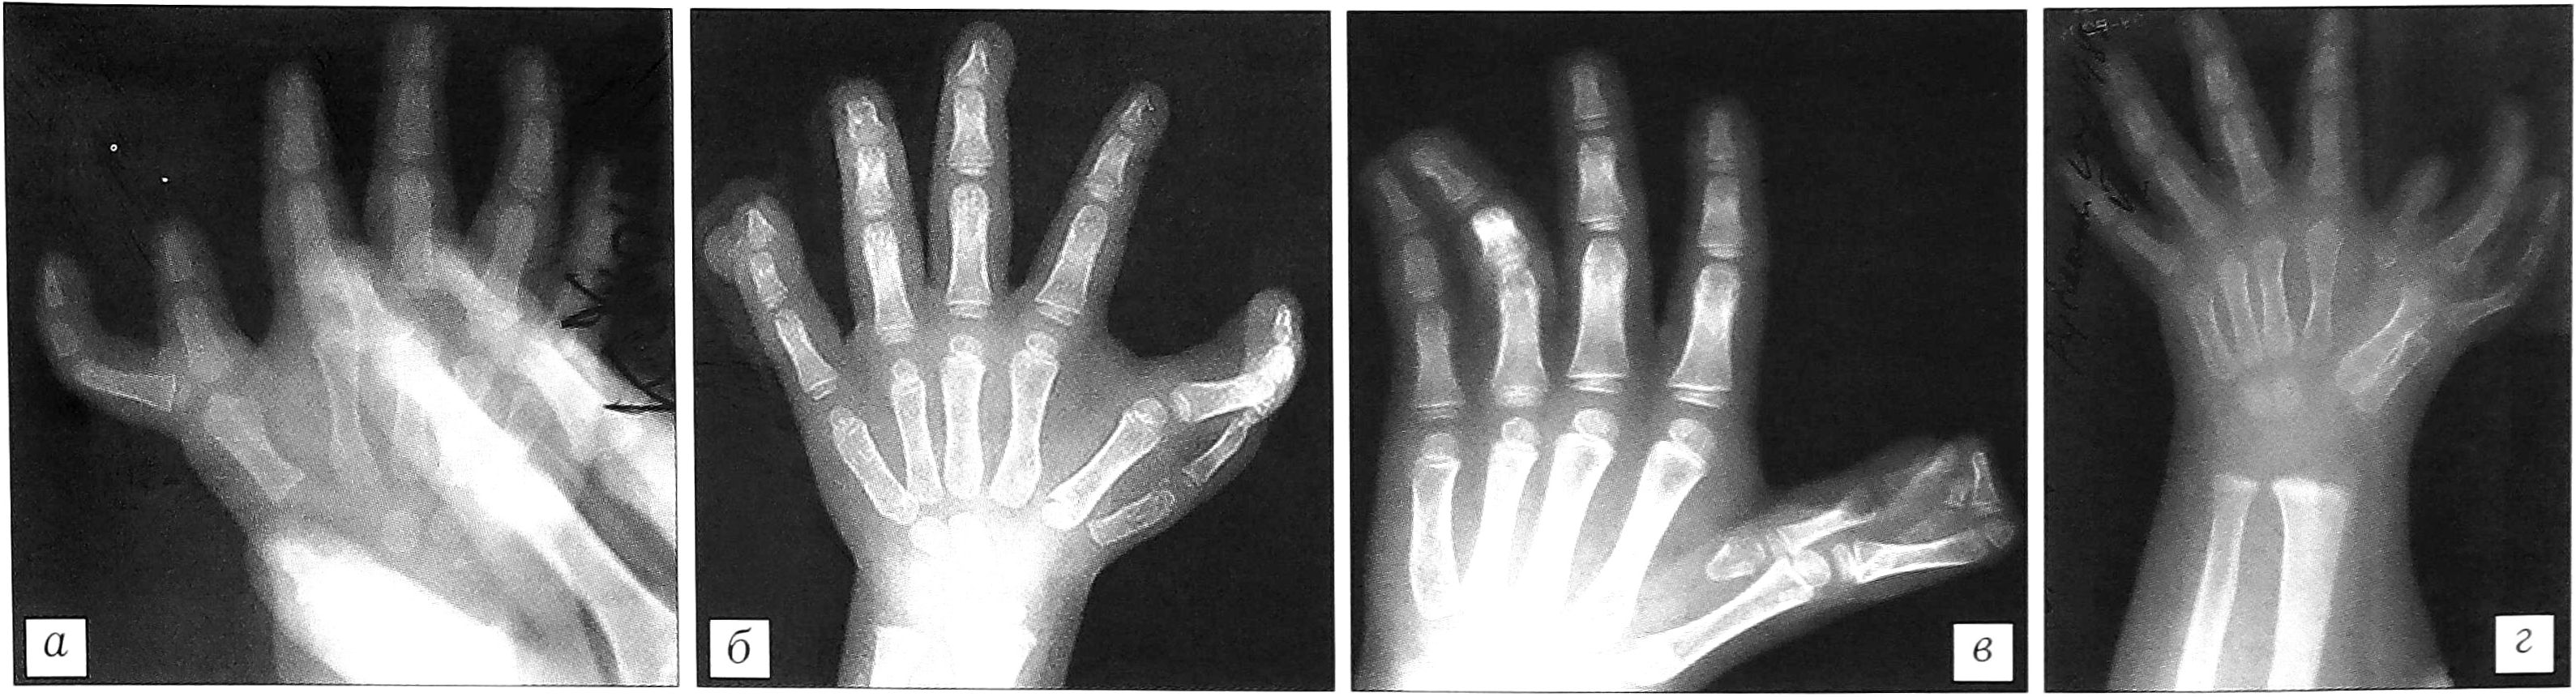

- Сочетание трехфалангизма с гипоплазией. Нами выявлены две формы сочетания трехфалангизма большого пальца кисти с его гипоплазией — брахимезофалангеалъная и долихофалангеальная, которые имеют большое сходство и характеризуются следующими признаками (рис. 6):

- продольные размеры I пястной кости всегда нормальные при брахимезофалангеальной форме, нормальные или умеренно увеличенные (до 20%) при долихофалангеальной форме; поперечные размеры уменьшены (до 30% от возрастной нормы);

- пястная кость имеет проксимальный эпифиз или псевдоэпифиз;

- размеры дополнительной фаланги равны или приближаются к размерам дистальной фаланги при брахимезофалангеальной форме и увеличены при долихофалангеальной (на 10-70%);

- форма фаланги прямоугольная, крайне редко овальная;

- продольные размеры I луча кисти соответствуют возрастной норме;

- величина первого межпястного промежутка уменьшена (редко при долихофалангеальной форме может соответствовать норме).

Рис. 6. Сочетание трехфалангизма с гипоплазией I луча. а — сочетание брахимезофалан- геальной формы трехфалангиз- ма с гипоплазией I луча; б — сочетание долихофаланге- альной формы трехфалангизма с гипоплазией фаланг, нормально развитыми I пястной костью и запястно-пястным суставом; в — сочетание долихофаланге- альной формы трехфалангизма с гипоплазией I луча.

Продольные размеры основной фаланги при долихофалангеальной форме нормальные или незначительно увеличены (до 10%), дистальной — значительно уменьшены (до 30%). При сочетании брахимезофалангеальной формы трехфалангизма с гипоплазией отмечается гипоплазия всего I луча. При долихофалангеальной форме возможны два варианта: 1) гипоплазия всего первого луча; 2) гипоплазия фаланг с нормально развитыми I пястной костью и запястно-пястным суставом (величина первого межпястного промежутка соответствует норме).